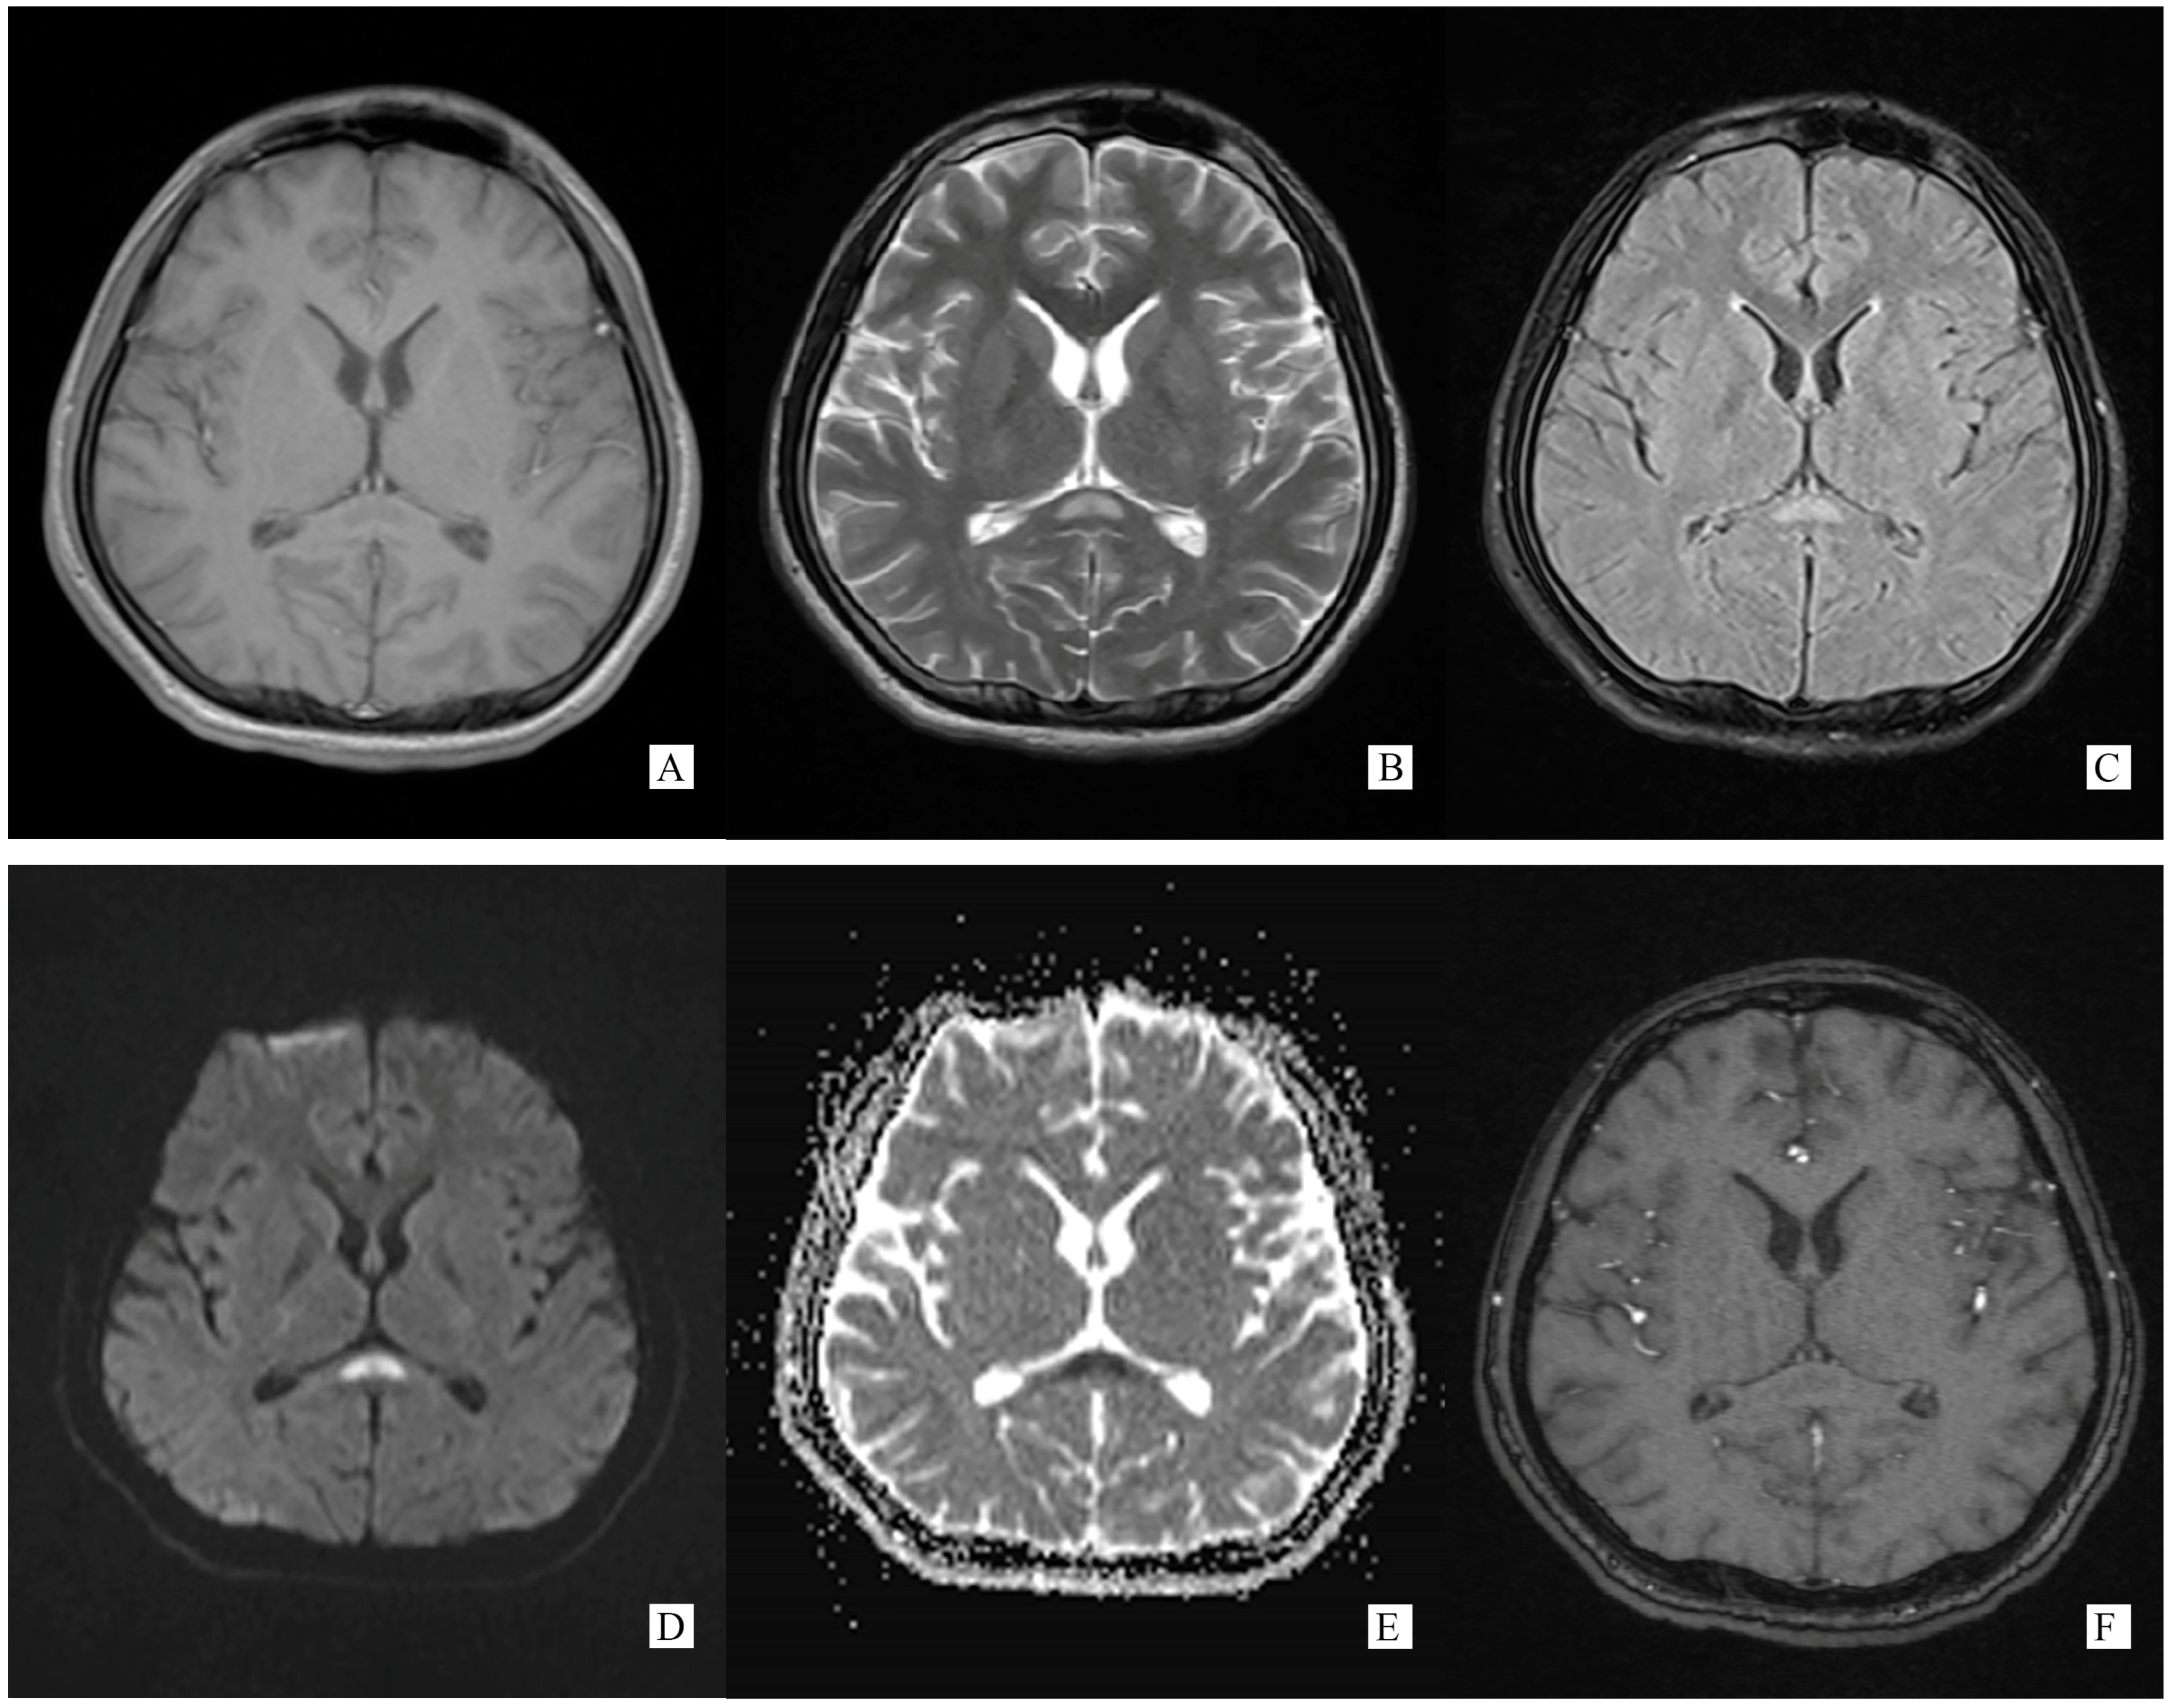

Figure 2.

(Performed on 13 November 2021) SCC lesion totally disappeared on brain MRI ((A). T1WI, (B). T2WI, (C). T2 flair, (D). DWI, (E). Post-gadolinium T1-weighted).

A repeated spinal tap was performed on 11 November 2021, which showed increased intracranial pressure, CSF glucose was still below normal contents, while CSF protein and chloride was lower than before and still abnormal (ICP 330 mmH2O, Glu 2.14 mmol/L, Cl− 119.50 mmol/L, Pro 1.05 g/L). WBC counts increased to 500 × 106/L. CSF screen using next-generation sequencing (NGS) indicated no infection. The CSF test of neural auto-antibodies revealed positive anti-GFAP antibodies (antibody titer 1:32), while the serum test was negative. CSF Ig electrophoresis revealed positive IgG oligoclonal bands (≥2 bands). A second cerebral MRI was performed on 13 November 2021 showing totally disappeared on SCC lesion (Figure 2).

Generally, typical features of autoimmune GFAP astrocytopathy present as a linear, radial perivascular enhancement pattern on brain MRI, and central longitudinally extensive enhancement pattern on spinal cord MRI [7]. RESLES is typically classified into two patterns on MRI: type I is an isolated lesion on SCC, type II is a lesion in SCC expending to callosal fibers, cerebral white matters or anterior portion of corpus callosum. No matter type I or type II, lesions can be significantly shrunk or totally disappeared within a month, accompanied with the relief of symptoms [8]. In the MRI of our case, the lesion was located in the SCC, manifested a hypointense signal on T1WI and hyperintense on T2WI and DWI, reversibly, which is similar to type I RESLES, but unlike the typical autoimmune GFAP astrocytopathy.